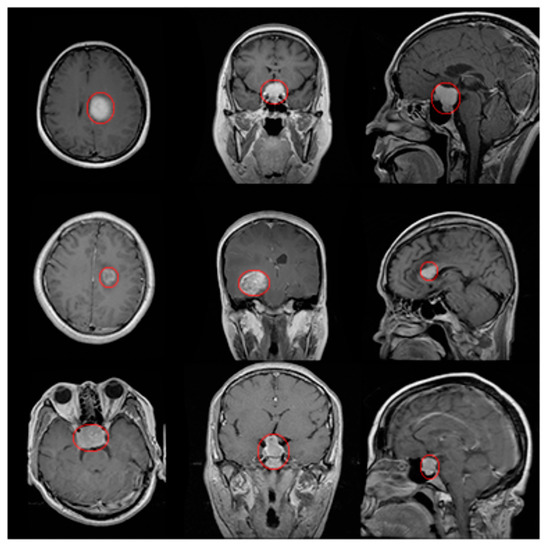

| Tumor Type/Plane | Axial | Coronal | Sagittal |

|---|---|---|---|

| Meningioma | 0.913 | 0.923 | 0.985 |

| Glioma | 0.939 | 0.940 | 0.986 |

| Pituitary | 0.947 | 0.943 | 0.909 |